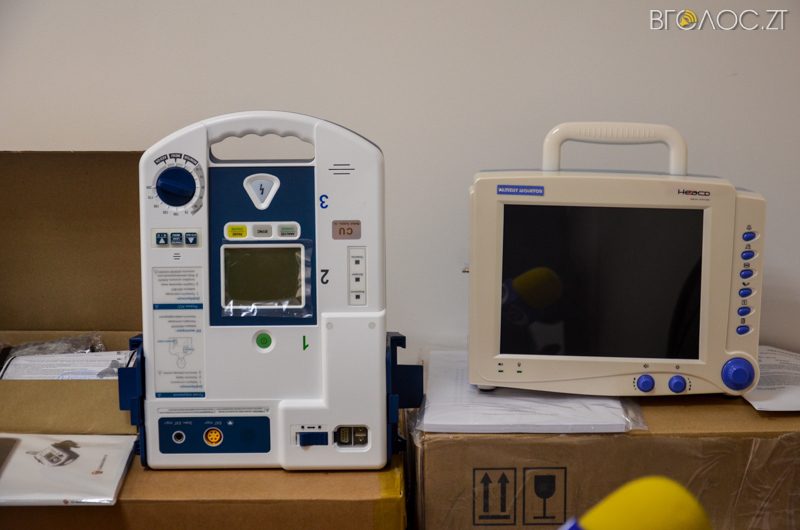

За словами головного метролога обласної лікарні Олександра Левандовського, на зекономлені кошти від придбання МРТ, а це – 1,2 млн грн – придбали інше необхідне обладнання для лікарні. Це – інфузійний насос, експрес-аналіз для визначення інфаркта міокарда, який дозволяє поставити діагноз пацієнту упродовж 5 – 7 хвилин, що раніше було неможливим. Також придбали монітор пацієнта, який показує його стан (температуру, тиск тощо), дефібрилятор, інгалятор, обладнання для лабораторії.